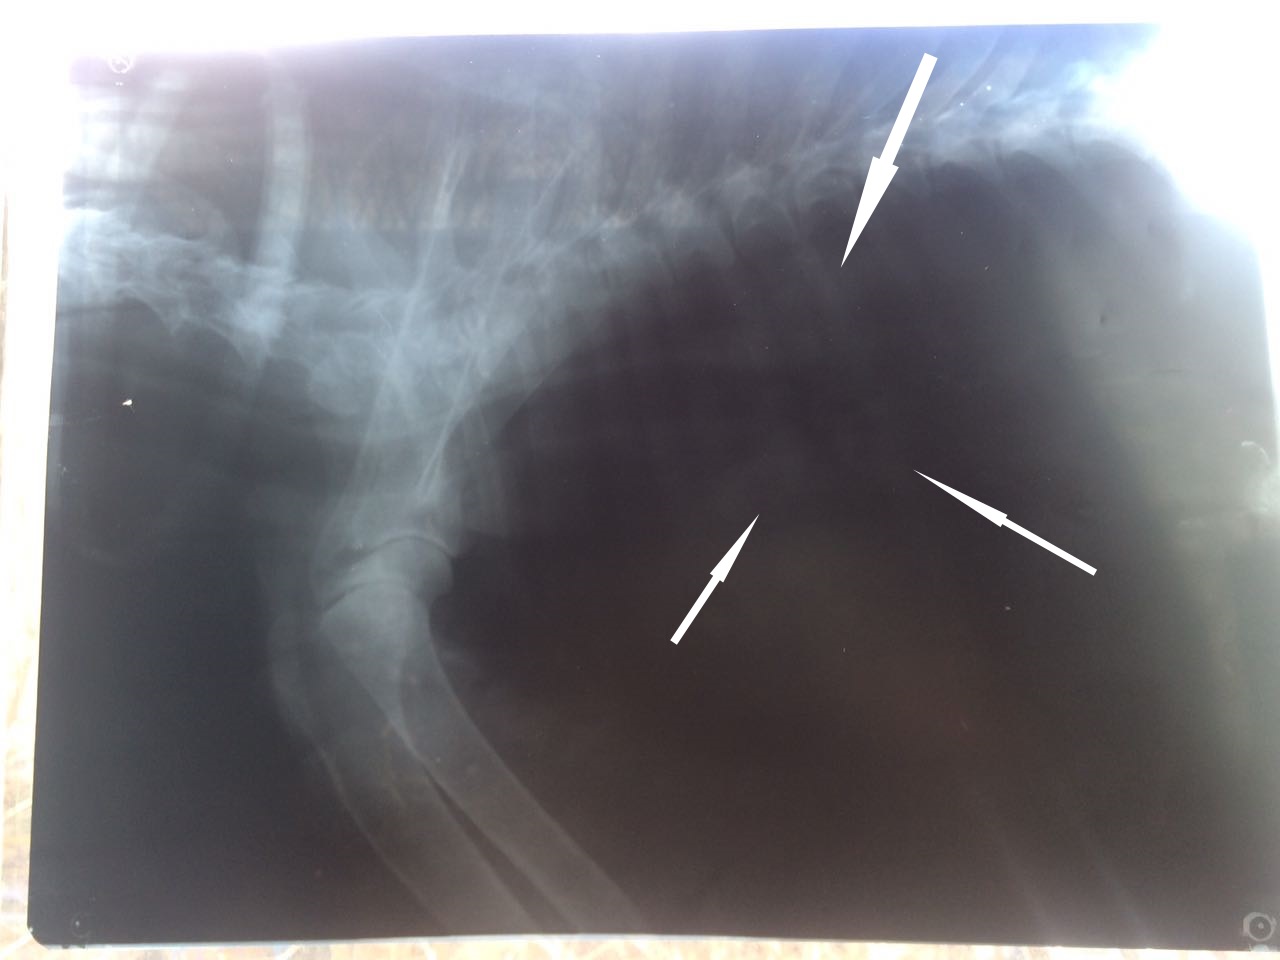

Легкие чистые на рентгене,но не совсем понятная история с образованием между вокруг пищевода и возможно это давит на трахею.На снимке отметила стрелочками.Что то наверняка,слизь или возможно еще что-то рентген не может рассказать окончательно.Во всяком случае в этом качестве.Конечно я бы сделала ей цифровой,но пока такой возможности нет.А МРТ уж слишком дорогое удовольствие и наркоз.